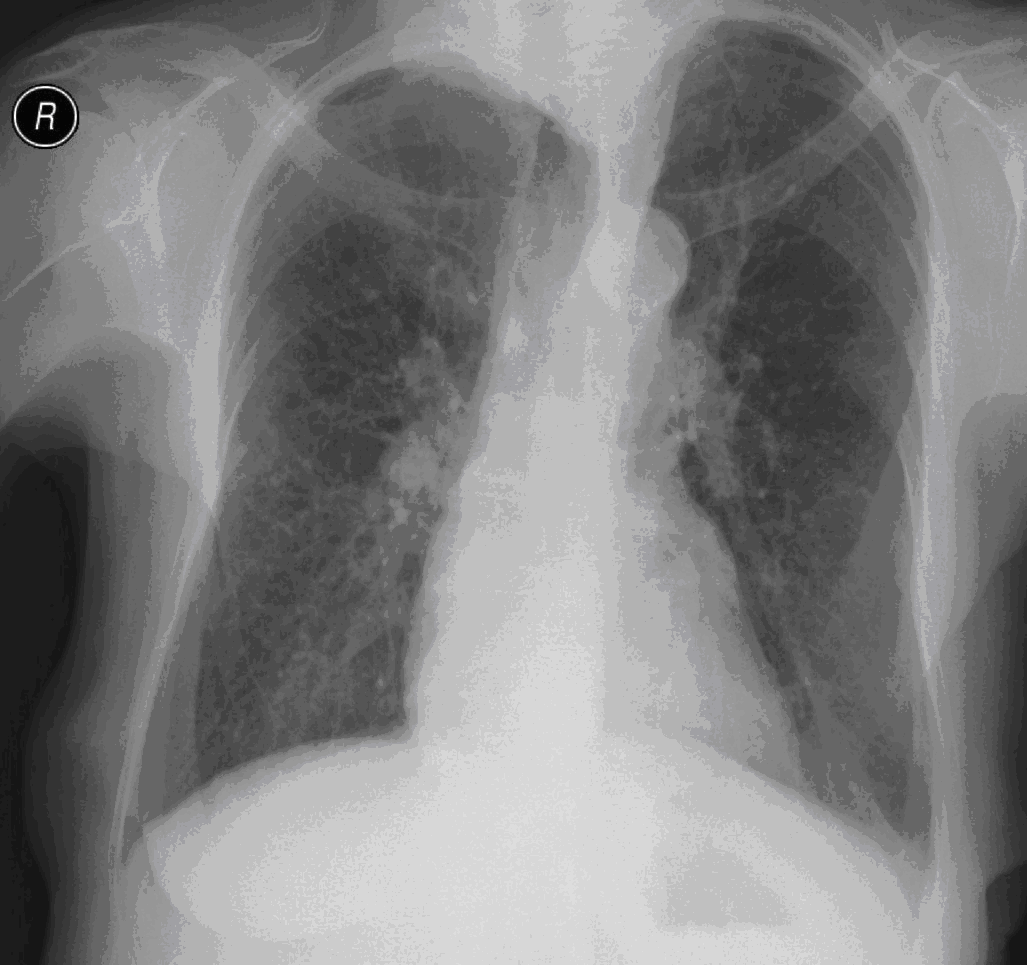

19. Tuberculosis, bidirectional chest radiographs and HRCT. (coronal reconstruction)

75 year old man: hx of hypertension, smoking. Symptoms: dyspnea, productive cough. Moist rales of auscultatory findings above the LLL, tension irritability in the level of lower dorsal spine.

a.) Chest radiograph, bilateral: Mild increased vascular markings. Extensive patchy lobar infiltration in the RUL Previous TB specific lesions in the left apex. The diaphragm contour is blurry on the right side (appr. 4 finger-wide pleural effusion). Cardiomegaly. Medium large dilated sclerotic aorta.

b.) HRCT: Reticular pattern of 10x10x5 cm area in the right apex (1st segment), (septal thickenings), mosaic-like ground glass opacity in the righ apex. Subpleural total atelectasis (mainly 1st segment): irregular mainly nodular soft tissue streak associated with the pleura (max. appr. 1 cm thickness). Some tiny subpleural emphysematous bullae in the right apex.